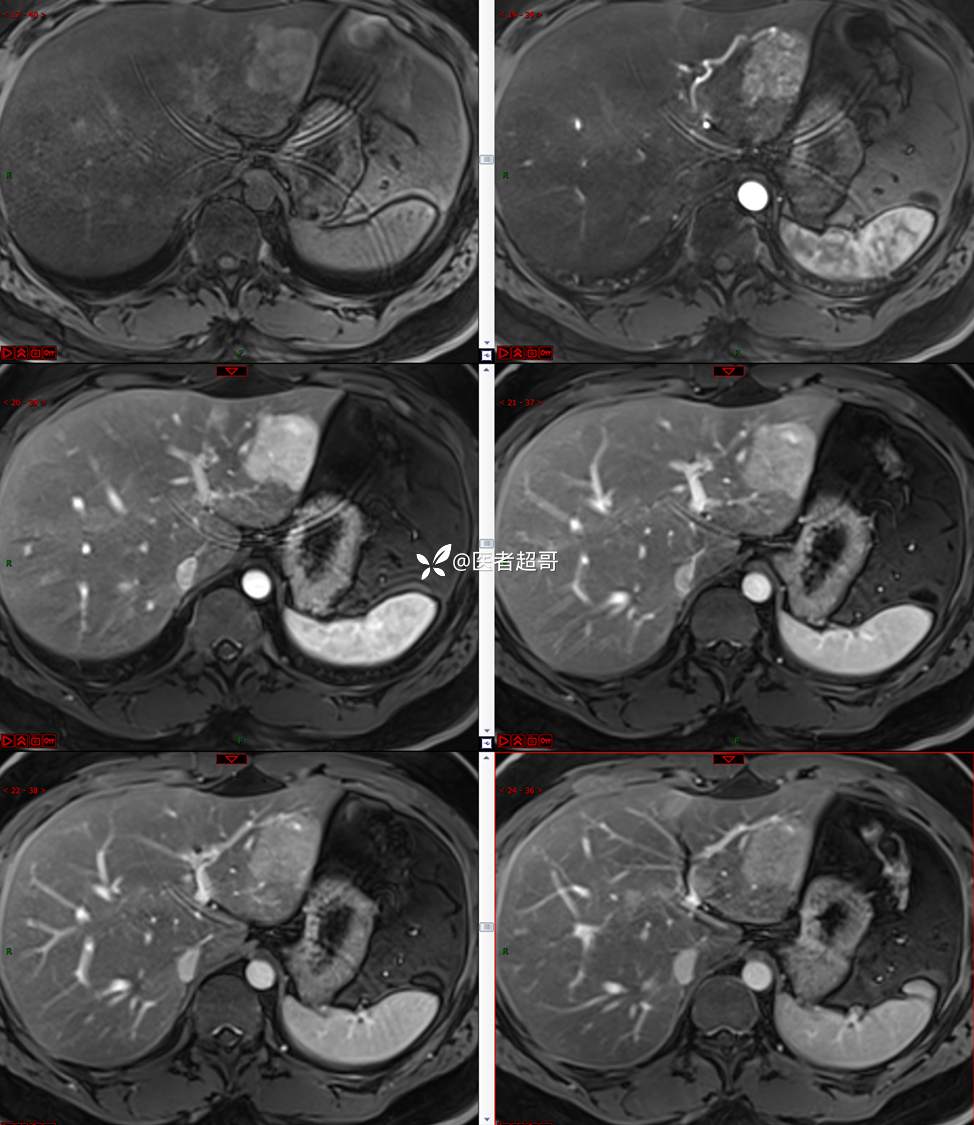

【影诊笔记685】男,31y,发现肝占位性病变5天就诊,请诊断分析,有病理结果!

主 诉:发现肝占位性病变5天。

现病史:患者缘于5天前体检时发现肝占位性病变,未予以特殊处置。现患者为求系统诊治就诊于我院,行普美显提示:肝左叶富血供占位,请结合临床及其他检查,肝多发血管瘤,脂肪肝,肝囊肿,请结合临床。门诊以“肝占位性病变”收入我科。病程中,饮食睡眠可,二便可,近期体重未见明显变化。